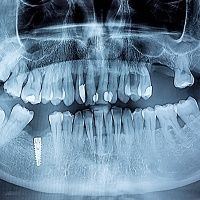

Scientists may have found a new way to treat severe cases of periodontitis.

A study published last month in Langmuir, a journal of the American Chemical Society, found that silicon nitride can have a lethal effect on the bacteria that commonly cause periodontitis.

Silicon nitride is a ceramic material used in spinal implants.

The study was conducted by researchers at the Kyoto Institute of Technology in Japan. According to the ACS, the study showed that the ceramic material changes the metabolism of Porphyromonas gigivalis, the bacteria that’s primarily responsible for periodontitis.

Surface chemical reactions at the surface caused the bacteria’s nucleic acids to degrade, drastically reducing the amounts of certain proteins and fats, the ACA said. Though it’s not yet known how the insights can be applied directly to dentistry, some speculate that the incorporation of silicon nitride into prosthetics might limit subsequent cases of periodontitis. The researchers say their study makes clear that silicon nitride holds promise as a treatment aid for patients with severe gum disease.

That could be a huge deal for the nation’s oral health. The US Centers for Disease Control and Prevention estimates that half of Americans age 30 and older have periodontitis, amounting to roughly 65 million people.